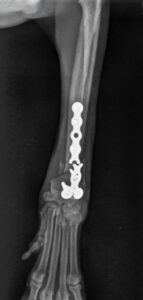

Doch drei Wochen später wurde der kleine Hund erneut im Notdienst vorgestellt: Beim Gassigehen hatte er auf einmal gelahmt. Die Ursache: ein Ermüdungsbruch der Metallplatte. „An Hugo sieht man, was passiert, wenn der tierärztliche Rat zur Ruhigstellung nicht befolgt wird“, sagt Dr. Klaus Zahn. „Übermäßige Aktivität hatte die Platte überlastet.“ Denn der Prager Rattler durfte viel zu früh wieder frei im Zimmer herumlaufen und sogar vom Sofa springen. „So kleine Hunde gehören für vier bis sechs Wochen in einen Laufstall, damit die Knochen stabil heilen können“, erklärt der Orthopäde.

Bei der Nachoperation setzte Chirurg Maximilian Herion statt der gebrochenen Platte eine identische neue ein. Die Verwendung eines dickeren Implantats verbot sich wegen Hugos filigranem Knochen. Auch diesmal verlief die OP erfolgreich. So dass wir Hugo samt Herrchen mit guten Wünschen und einer erneuten Ermahnung, den Hund in einem Kinderlaufstall oder Käfig zu halten, nach Hause verabschieden konnten.